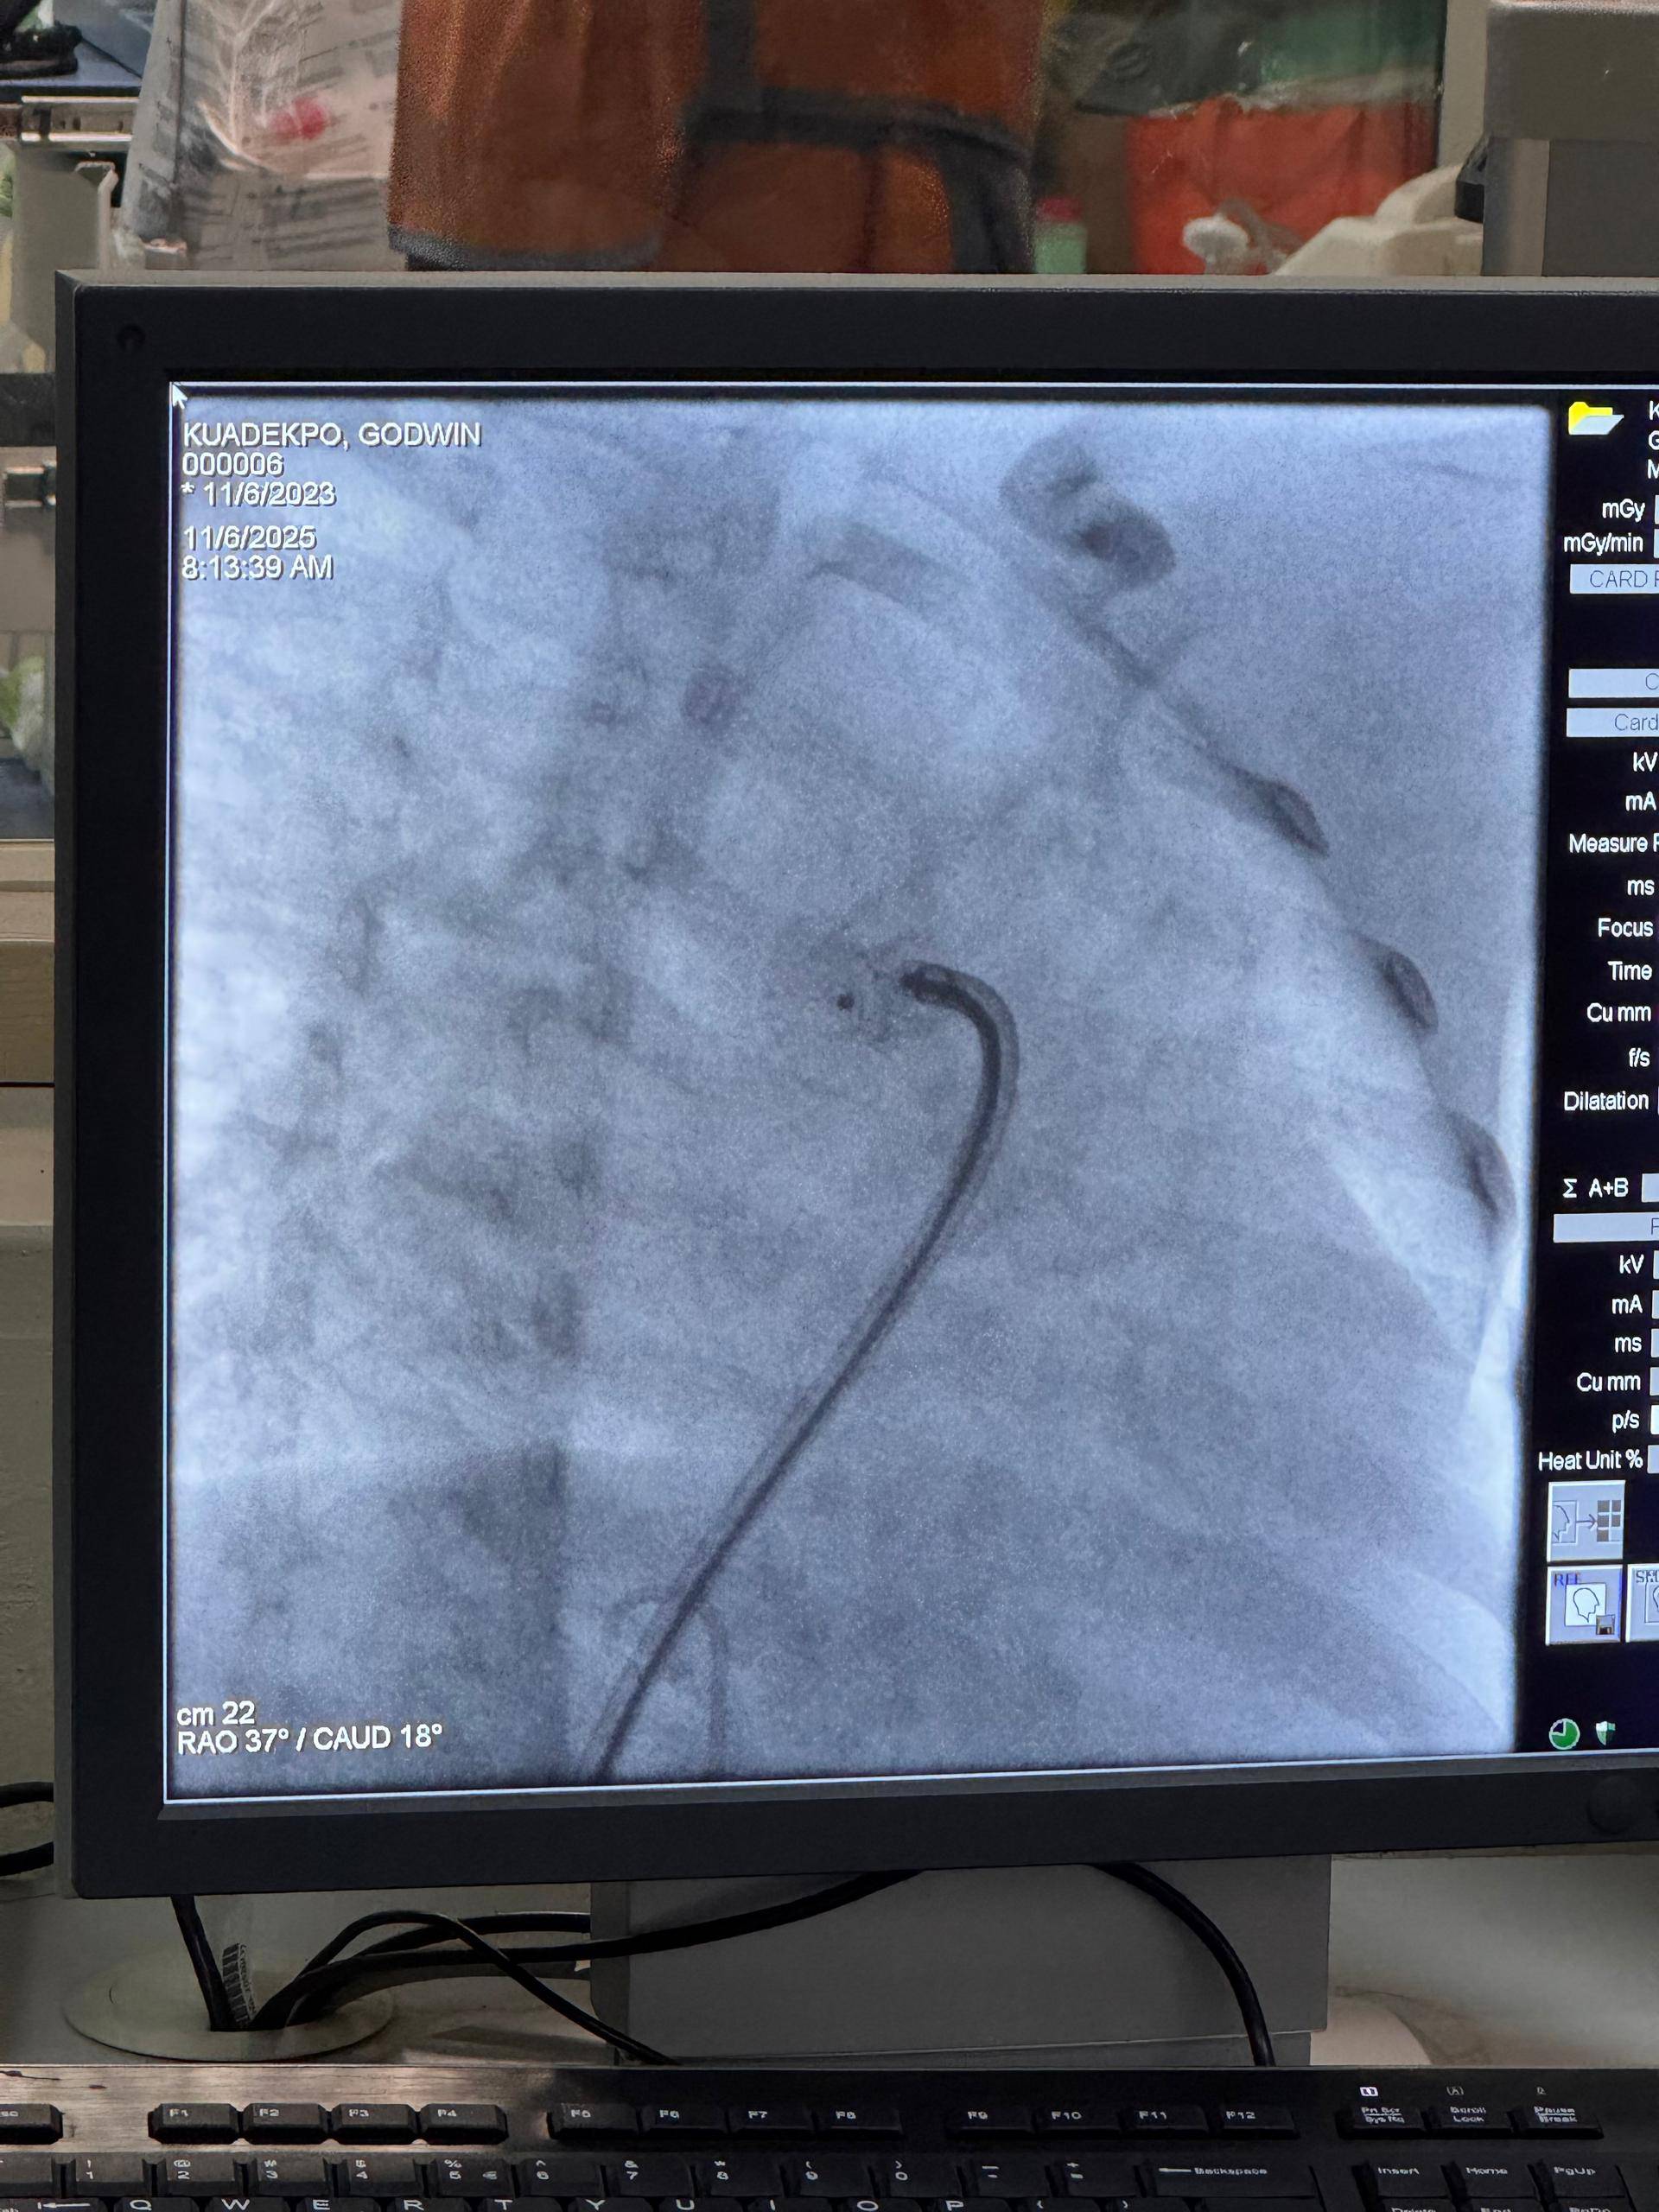

Katharina Kaufmann und Katrin Krüger, Verwaltungsleitung der Deutschen Internationalen Schule Accra (GISA), besuchten das aktuelle Projekt der Gerald-Asamoah-Stiftung für herzkranke Kinder im Korle Bu Teaching Hospital in Accra.

Beide zeigten sich tief beeindruckt von der Professionalität, dem Engagement und der Menschlichkeit des gesamten Teams. Seit vielen Jahren unterstützt die Stiftung mit Ärzten und Pflegekräften aus Deutschland Kinder in Ghana, die an angeborenen Herzfehlern leiden – und schenkt ihnen durch lebensrettende Operationen neue Hoffnung.